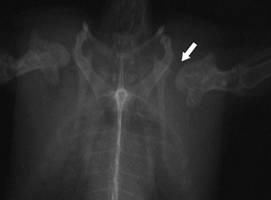

Torn ligament

between humerus and shoulder joint. Observe the dislocation

of the left humerus head of the shoulder joint |

Fracture of the

clavicula and the coracoid: multiple

fractures happen

frequently during flying onto

something